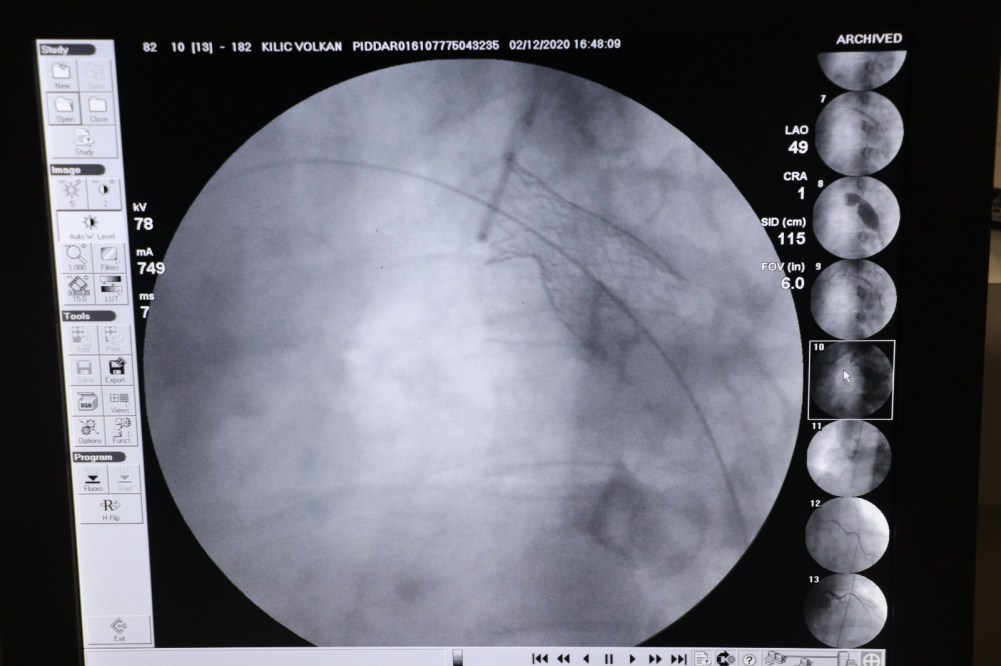

Son olarak geldiği Özel Echomar Hastanesi Doktorlarından Kardiyolog Doçent Doktor Mehmet Yaman’a muayene olan Volkan Kılıç’ın alpten çıkan aort damarının doğuştan dar olduğu tespit edildi. Yurt dışından getirtilen özel stentlerin Anjiyo yöntemi ile takılmasının ardından Volkan Kılıç’ın sağlığına kavuştuğu ifade edildi.

Yaman konuşmasında “Volkan kardeşimiz 39 yaşında erkek hastamız. Şimdiye kadar düşmeyen Hiper tansiyon şikâyeti ile hastanemize başvurdu. Yaptığımız tetkiklerde kalpten çıkan aort damarının doğuştan dar olduğunu tespit ettik. Çok nadir görülen bir konudur. 40 ve 50’li yaşlarda çok ciddi rahatsızlıklara neden olur. Birçok yandaş hastalıklara da neden olur bur hastalık. Gerekli tedavinin yapılamaması durumunda Beyin kanaması, kalp yetmezliği gibi ölümcül hastalıklara neden olur. Bunu tespit eder etmez müdahale ettik. Bu hastalığın iki ameliyat şekli var. Birisi kapalı diğeri açık ameliyat. Açık ameliyatta hastanın felç olma durumu söz konusuydu. O yüzden açık ameliyat çok önerilmiyor. Kapalı ameliyat ise özel stentlerle yapılıyor. Volkan bey stentlerini özel bir sipariş ile yurt dışından getirttirdik. İşlemi burada ameliyatsız Anjiyo yönetimi ile yaptık. Şu anda hiçbir sıkıntısı yok: Sağlığına kavuştu. Çok sıkıntıları olmuş. Ancak hayati bir sıkıntı yaşamamış olması, felç geçirmemiş veya ölmemiş olması kendisi için büyük bir şans” dedi.